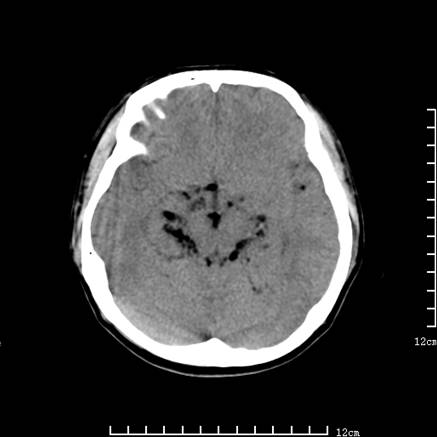

以下是引用jiajie在2008-9-5 22:25:00的发言:[br]男,22岁,头痛1月余。脑室、脑池内病变ct值约-120hu。[br][br]双侧侧脑室内低密度影充填,出现脑脊液脂肪平面,脑池内亦可见弥散分布的斑点状低密度影,脑室脑池未见明显扩大。[br]考虑胆脂瘤破裂后内容物进入脑脊液。